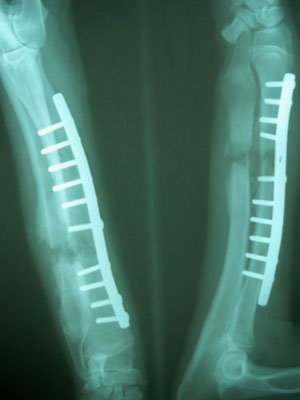

Στις 5/12/09 πραγματοποιήθηκε ορθοπεδικό χειρουργείο.Προνάρκωση του ζώου έγινε με ξυλαζίνη και ατροπίνη, η εγκατάσταση της αναισθησίας με πεντοθάλη 2,5% και διατήρηση της αναισθησίας με εισπνεύσιμο αναισθητικό (ισοφλουράνιο).Διεγχειρητικά χορηγήθηκε TOLFENDINE 3ml, DALACIN 10mg/kg και MARBOCYL 3ml.

Aποκατάσταση του κατάγματος έγινε με τοποθέτηση μεταλλικής πλάκας στην έσω επιφάνεια της κερκίδας με 6 κοχλίες στο κεντρικό τμήμα και 4 κοχλίες στο περιφερικό τμήμα.

Μετεγχειρητικά χορηγήθηκε για 5 ημέρες DALACIN 10mg/kg BID.